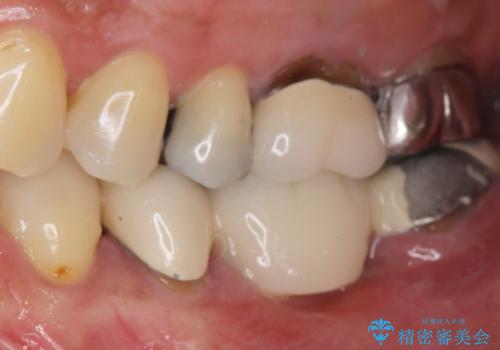

- 奥歯の痛みを主訴に来院された患者様です。

精査したところ、ブリッジの支台歯となっている左下の奥歯(左下7)は大きなう蝕により神経が死んでいました。

根管治療後、メタルボンドブリッジによる補綴治療を行いました。